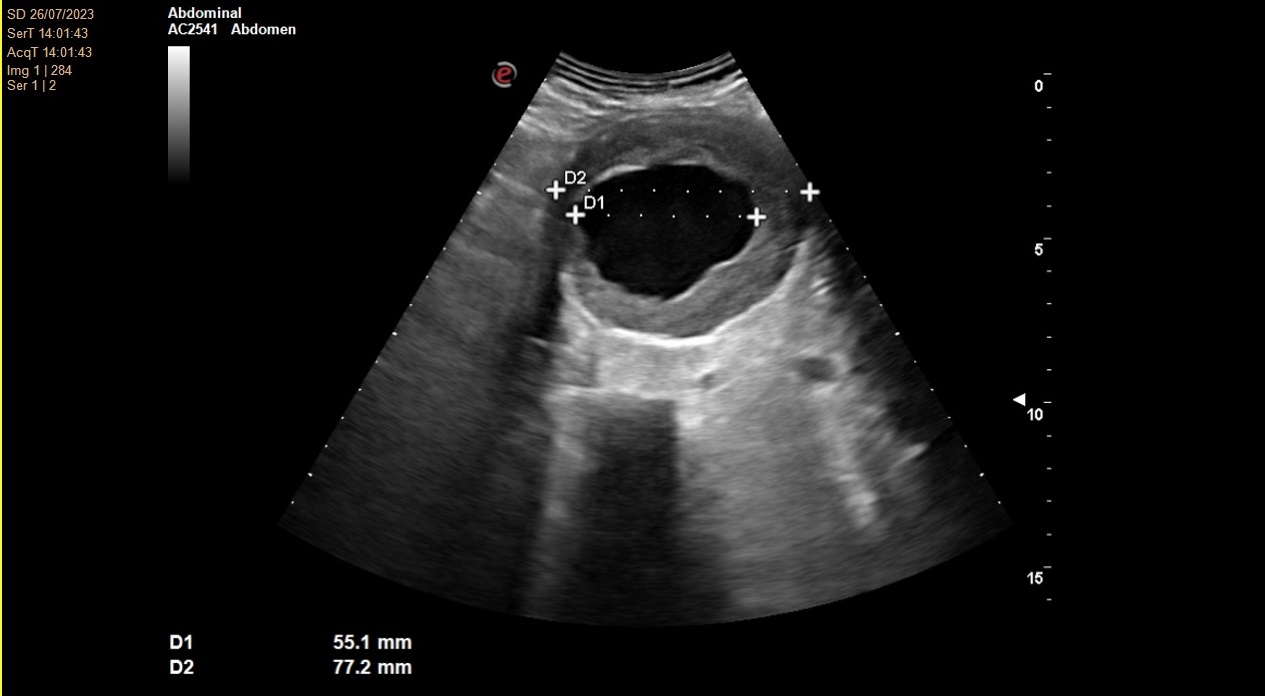

No se consigue visualizar el lóbulo hepático izquierdo ni páncreas por interposición de gas intestinal. Lóbulo hepático derecho de ecogenicidad y ecoestructura normal. Vesícula biliar de paredes finas y lisas sin contenido en su interior. Vía biliar no dilatada. Se visualiza una arteria aorta a nivel abdominal de un tamaño de 78 x 77 mm en su diámetro máximo.

Angio TC toracoabdominal en el que se observa una dilatación aneurismática de 73,8 mm de morfología fusiforme infrarenal hasta bifurcación ilíaca con trombosis mural concéntrica en toda su extensión.